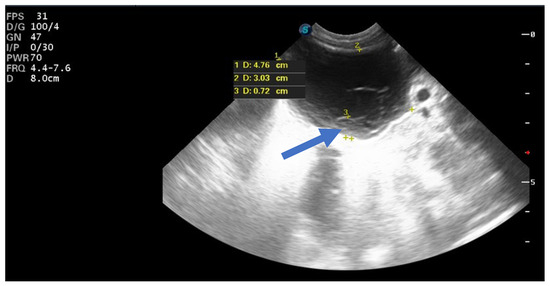

Of the nine simple cysts, seven regressed spontaneously within the first two months after birth (Figure 5 and Figure 6).

Figure 5.

Ultrasound image of a simple cyst with an intracystic blood clot (arrow) at the age of 2 weeks postpartum, which regressed spontaneously at 2 months.

Figure 6.

Ultrasound image of a neonatal simple cyst with a daughter cyst (blue arrow), which regressed spontaneously after 2 months.